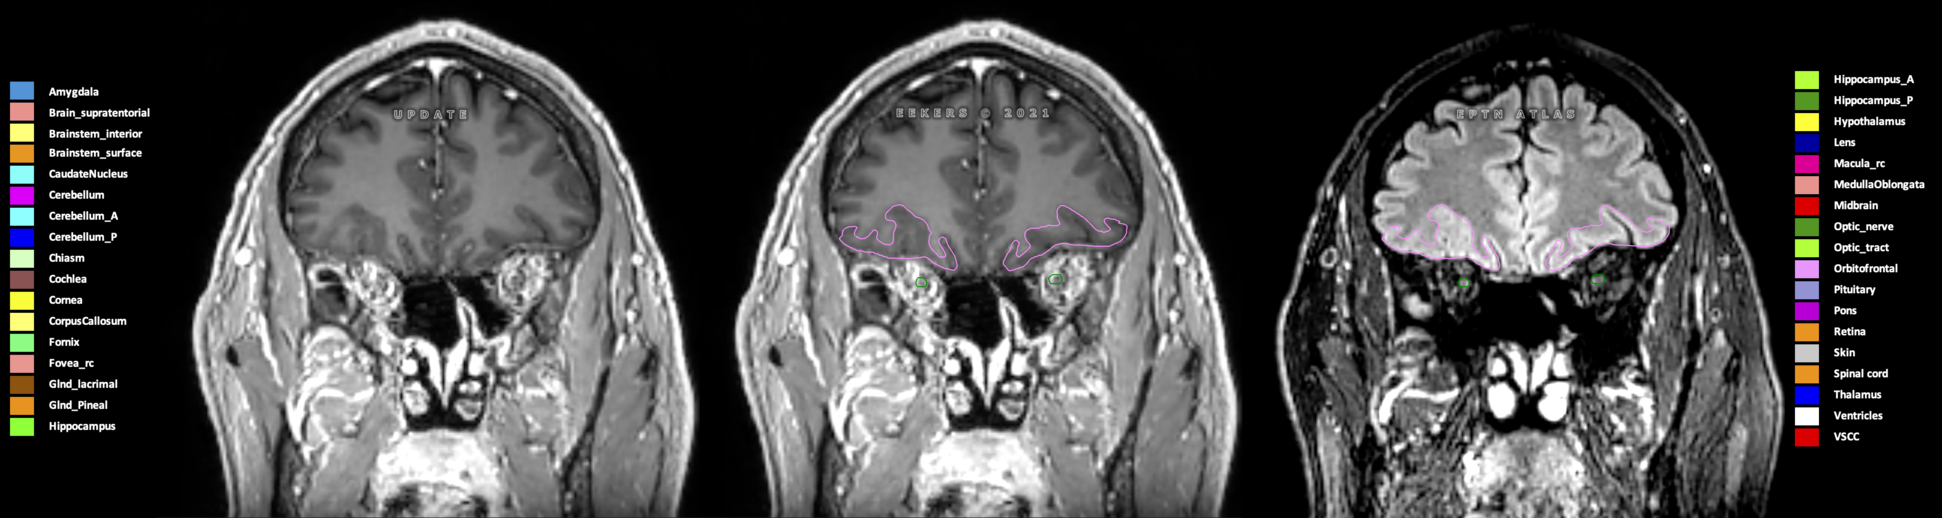

Eekers et al. have published an international neurological atlas for contouring of organs at risk in consensus with the European Particle Therapy Network (EPTN) in 2018 and an update in 2021. The purpose of this consensus atlas is to decrease inter- and intra-observer variability in delineating OARs relevant for neuro-oncology.

Included are all OARs known to be relevant for radiation-induced toxicity in neuro-oncology: brain, brainstem (midbrain, pons, medulla oblongata), chiasm, cerebellum (anterior & posterior), cochlea, cornea, hippocampus (anterior & posterior), hypothalamus, lens, lacrimal gland, optic nerve, pituitary, skin, and vestibular & semicircular canals. To further facilitate research on cognition, vision and radiological changes after irradiation of the brain, potential clinically-relevant OARs are included: amygdala, caudate nucleus, cerebellum (anterior & posterior), corpus callosum, fornix, macula, optic tract, orbitofrontal cortex, periventricular space (PVS), pineal gland, and thalamus.

Three-dimensional delineation of the 25 consensus OARs for neuro-oncology are shown on CT (WW/WL 120/40, 3000/600), 3T MR images, (T1Gd, T2FLAIR 1mm) and 7T MR (MP2RAGE 0.7 mm). All are presented in transversal, sagittal and coronal view.